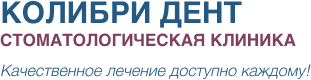

Перелечивание эндодонтически пролеченных зубов. Екатеринбург, 2014 г.

Современные протоколы эндодонтического лечения от диагностики до обтурации. Москва, 2021г.

Лечение пульпитов и периодонтитов. Пошаговые протоколы. Stom-Academy, 2022г.

Лечение кариеса, пульпита, периодонтита.